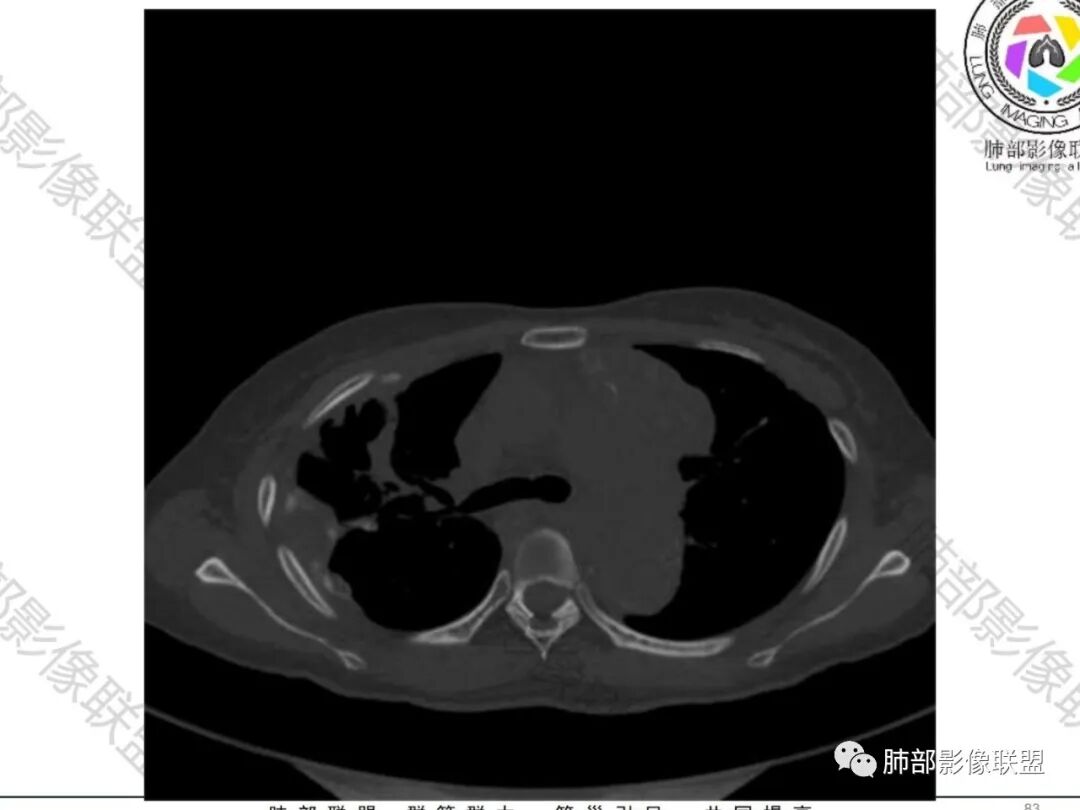

傅昌瑜:青年女性,咳嗽胸痛2月,偶有血痰。双肺上叶多发不规则肿块,密度不均匀,内部可见点状、条片状钙化影,右上肺病灶空洞,壁厚薄不均,见壁结节,与支气管关系不清,两侧胸膜增厚,见多发结节,部分结节边缘膨隆明显,结节内亦有多发钙化。上述改变常见于结核、尘肺、钙化性转移等疾病。有膨隆感的结节考虑转移可能性大。

尘缘:青年女性,痰中带血,胸痛2月,无发热盗汗,实验室检查,有贫血,总蛋白降低,血沉情况未知,肿标基本正常。影像表现:双上肺小叶间隔增厚,双侧胸膜广泛不规则增厚,胸膜下多发肿块伴不规则钙化,右侧肋骨破坏。纵隔淋巴结肿大不明显,双肺门淋巴结肿大,部分融合,分析思路:一、感染性病变,1、结核,青年女性,胸膜增厚,多发肿块伴钙化,有咳嗽胸痛,痰中带血,要考虑,但无结核中毒症状,病史仅两月却钙化太明显,肺内没有明显树芽征,存疑,2、其他感染,无炎性指标支持,白细胞不高,可能性小。二、非感染性病变,1、尘肺,胸膜增厚,钙化,胸膜下钙化性肿块,要考虑,但肺内无粉尘结节,无职业史,可能小。2、转移性钙化,无肾脏病史,无血清钙磷代谢异常指标支持,肺内间质无钙沉积改变,基本排除。三、肿瘤性病变,1、肺癌伴转移,双上肺有小叶间隔增厚,双肺门有淋巴结肿大,要考虑,但青年女性,病史两月,钙化太多太广泛,肿标基本正常,可能性小。2、骨肉瘤转移。15-30岁青年人,是骨肉瘤高发年龄,肺内多发成骨样钙化转移灶,双上肺小叶间隔增厚符合癌淋样表现,右侧肋骨破坏,要高度怀疑,需要详细询问病史及手术史。3、软骨来源肿瘤伴肺内转移,右侧肋骨虽有破坏,但无明显软骨样破坏及钙化。可能小。4、其他肿瘤伴转移,青年女性,其他恶性肿瘤能广泛发生钙化性转移的可能性小。综上所述:骨肉瘤伴右侧肋骨及胸膜转移,胸膜下转移,肺内癌淋可能最大,结核不完全除外,下一步需要,仔细询问病史,如果有骨肉瘤史,则基本确诊,如果没有,需要进一步问询呼吸系统症状,病程,以前的影像对照,了解肾脏情况,查血清钙磷指标。

右肺体积缩小,上叶见空洞影

内壁较光滑,但有壁结节

上叶内多个结块,边缘有膨隆,内有钙化灶

钙化灶密度较高,环形/结节状

胸膜及附近肺内见多发结节/斑块

密度类似

边缘膨隆

空洞——恶性特点

胸膜结块,有侵袭性

但是都有多发钙化

肋骨伴随有溶骨性/成骨性骨质破坏,常规还是要警惕恶性